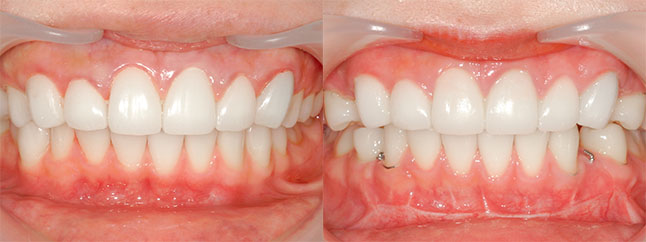

大阪府 22歳 女性

執刀医 辻和志

【治療内容】上のアゴと下のアゴの両方にこんもり感があったため、上下のアゴの骨をきって後ろに下げました。

【費用】上下セットバック 2,307,800円(税込)

【リスク】全身麻酔で行うため全身の健康状態が悪い方は行うことができません。また、手術当日は安静にしていただく必要があります。